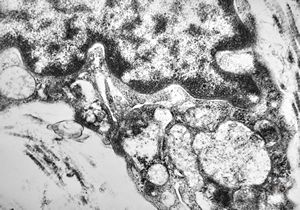

M, 28y. | leishmaniosis … skin of the cheek

M, 28y. | leishmaniosis … skin of the cheek